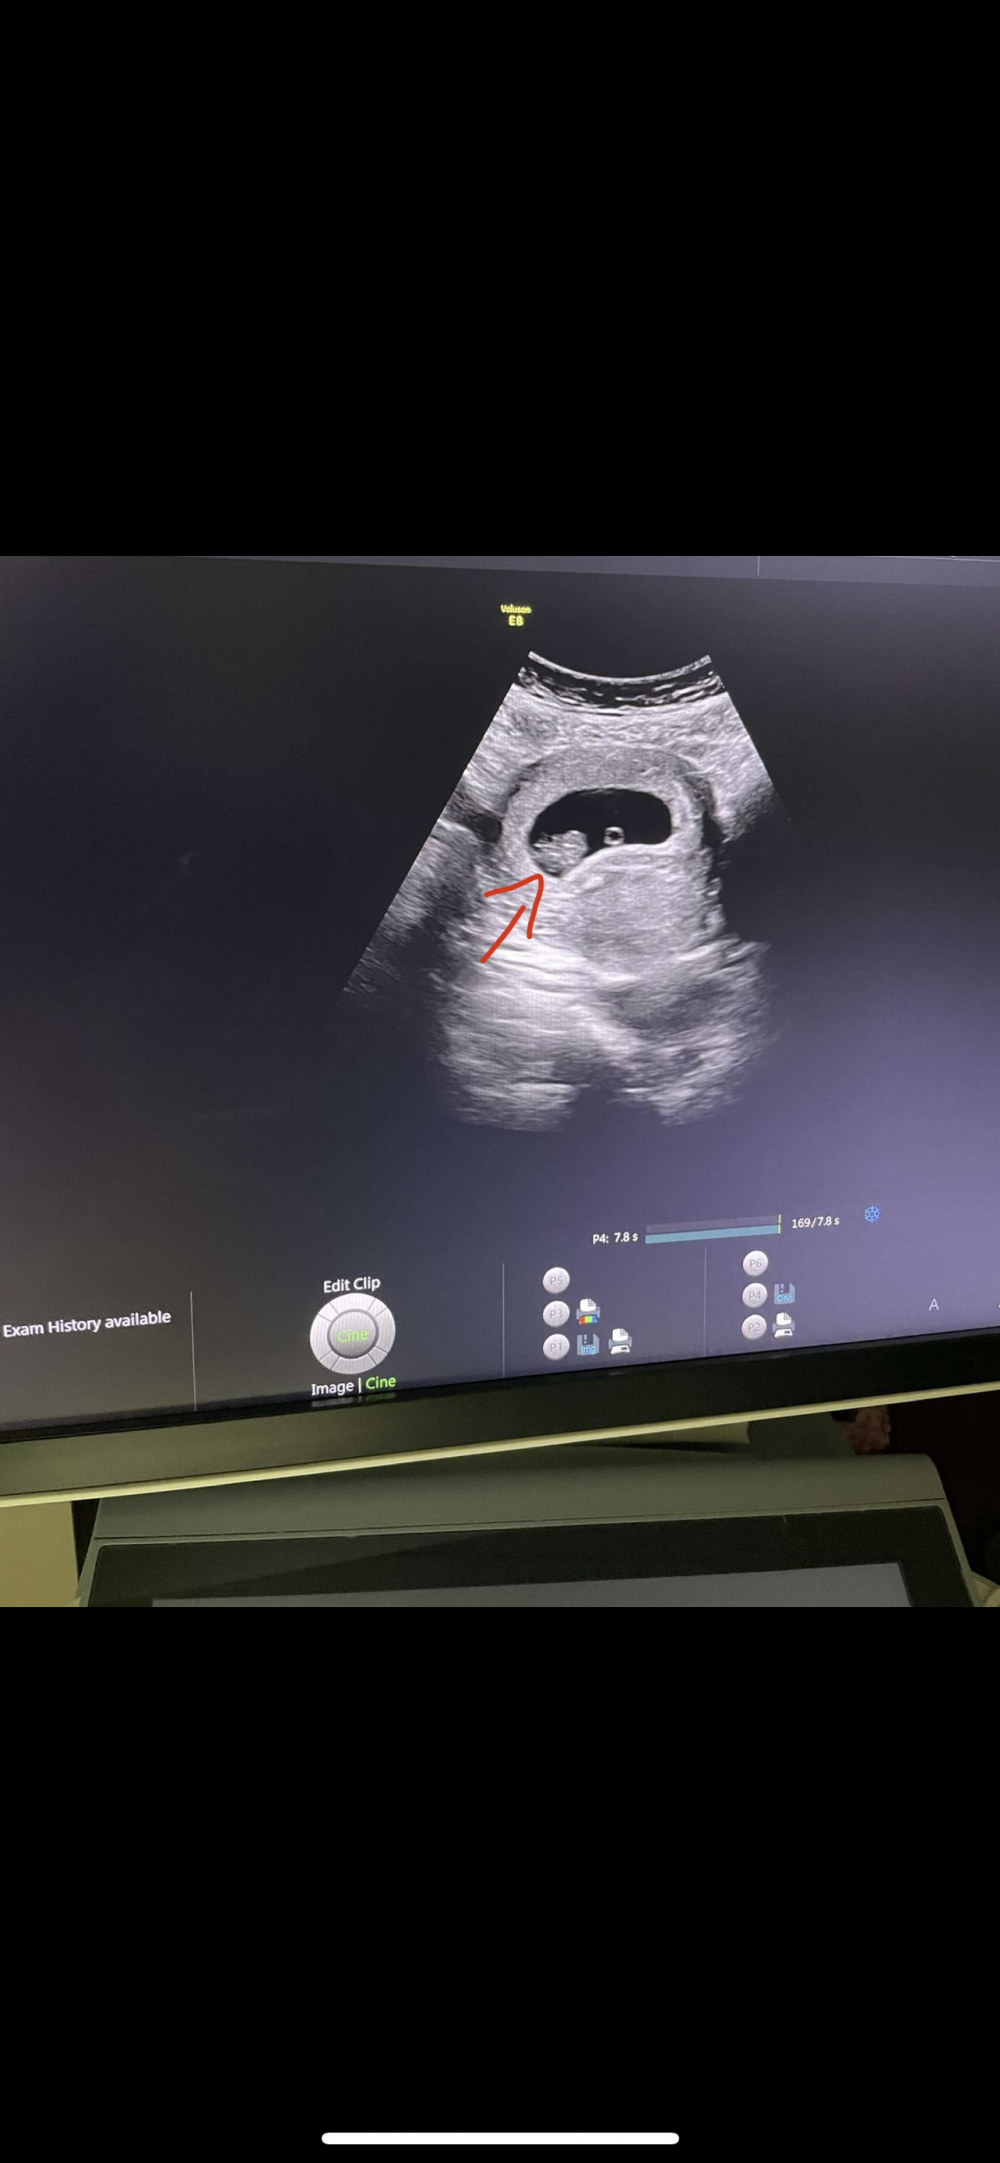

لوله يا قلبي سالتي بخصوص السونار هناك انا اسوي بينهم يومين ما منه ضرر ابد

سارونه طيب شوفي سوناري حتى لو تسليه عادي 😂